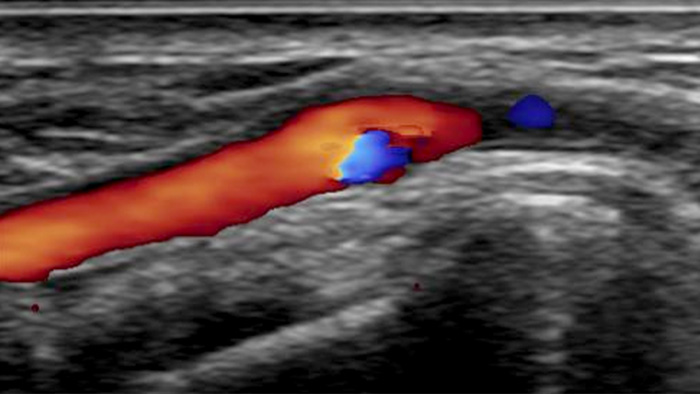

CX50 ultrasound system

A realistic visualisation of arterial vasculature is required to effectively access the arterial system. Our integrated CX50 ultrasound system provides premium quality images of the radial artery and veins to support radial access interventions.